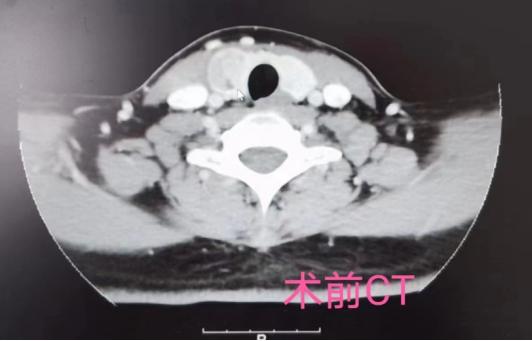

△术前CT影像

患者情况:罗某,女,28岁,因发现颈部无痛性肿物半年门诊入院。

患者于半年前发现颈部无痛性肿物,肿物渐大,心悸、气促、呼吸及吞咽受限等不适。外院查颈部财产提示甲状腺右叶囊实性结节,TI-RADS 3级。门诊行甲状腺结节US-FNA,未见癌。

专科查体:颈软,无抵抗,气管居中,右侧甲状腺可触及一个结节,约3x3cm,质中,边尚清,无压痛,随吞咽上下移动。左侧甲状腺未触及明显肿物,双侧颈部未触及肿大淋巴结。